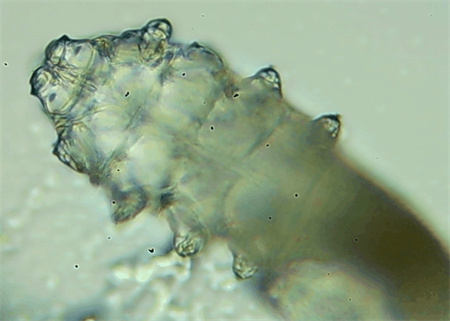

從一只眼睛的上眼瞼和下眼瞼處各拔3根睫毛,放在玻片上。

把玻片放到顯微鏡下觀察,通過電腦實時傳送的畫面,可以查看到這些拔下來的睫毛上是否有螨蟲。

結(jié)果,有6個人拔下來的睫毛上都發(fā)現(xiàn)了螨蟲。

這種螨蟲叫做蠕形螨,他們通常呈乳白色、半透明的細(xì)長狀,擁有四對腳。它們跟被子上的塵螨可不是同一種。

這些蠕形螨主要寄生在面部、頭皮、眼睛的睫毛毛囊、睫毛皮脂腺,以及瞼板腺里,以睫毛囊上皮細(xì)胞、腺體內(nèi)脂質(zhì)為食物。因此,即使經(jīng)常換洗床單、衣物,也可能會有蠕形螨。